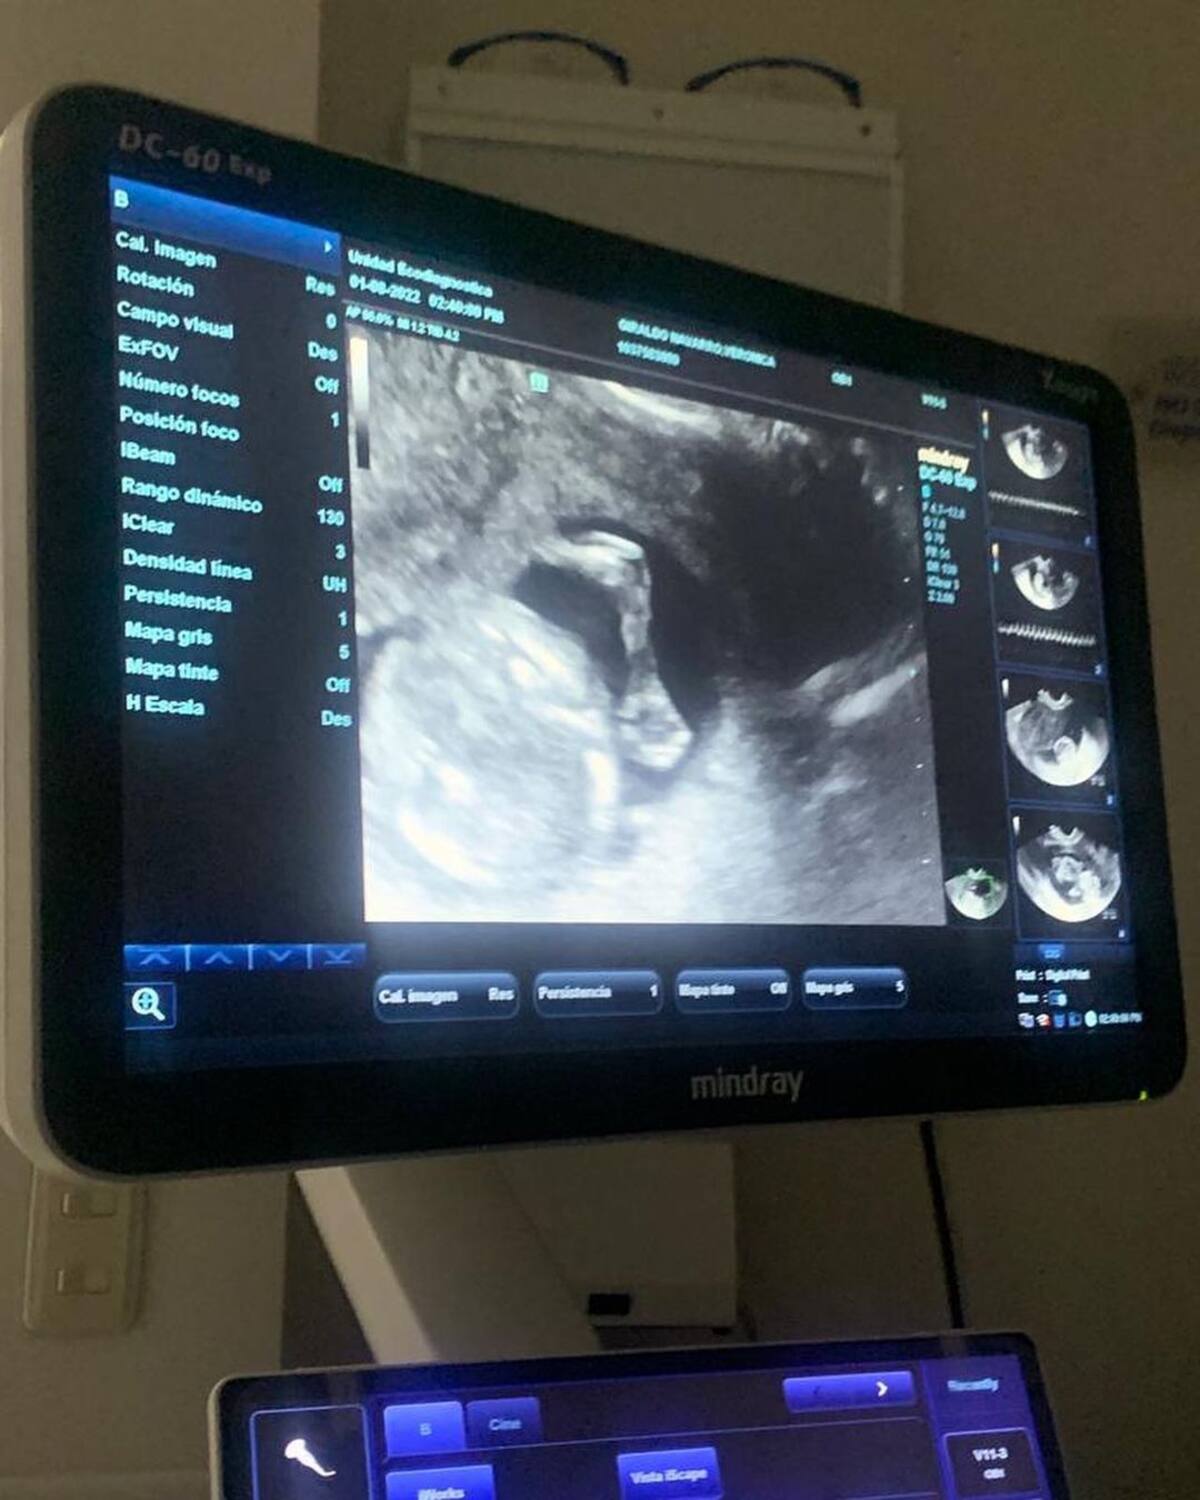

COLOMBIA.- Verónica Giraldo Navarro que recorrió algunos lugares del mundo junto a su hermana Karol G para despedir el pasado de la cantante gritó a los cuatro vientos que está embarazada.

Sí, así como lo lees, “La Bichota” se convertirá en tía por primera vez, así lo dio a conocer su hermana la mañana de este sábado, 13 de agosto por medio de su cuenta de Instagram donde externó lo feliz que estaba por esta nueva etapa en su vida.

Verónica detalló que recorrió varios países embarazada sin saberlo. De hecho, en diversos videos que publicó Karol G en sus historias de Instagram siempre estuvo de su hermana en todas sus aventuras donde conocieron los safaris de África entre leones, búfalos y leopardos, pasearon en globos aerostáticos y hasta se aventaron del paracaídas.

Recorrí unos hermosos países al lado tuyo, sin muchos saber que tú existías, pero para mi a sido la mejor noticia de la vida saber que soy mamá de un pequeño o pequeña bebe, que pronto sabremos si será Sophia o Emilio”, comenzó su mensaje la hermana de cantante.

Y añadió: “Para mí es hermoso contar esto porque para mí a sido una inmensa alegría saber que día a día en mi barriguita crece mi verdadero amor y un amor tan puro que día a día aprendo para él o para ella, y convirtiéndome en la mejor mamá del mundo para mi bebé”.